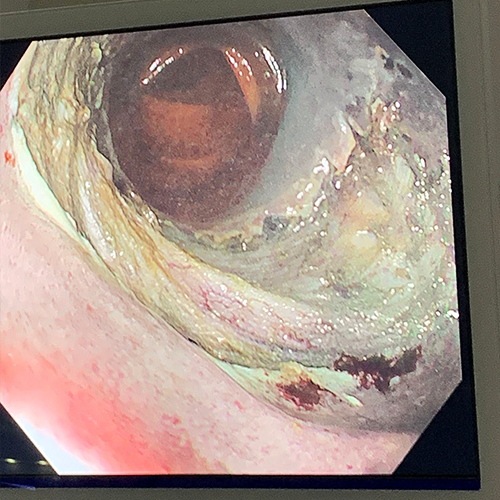

Dr Sergio Coda removed the lesion en bloc using Speedboat UltraSlim, leaving a clean muscle bed.

The lesion was non-granular laterally spreading tumour (LST-NG) and 40x20mm is size.